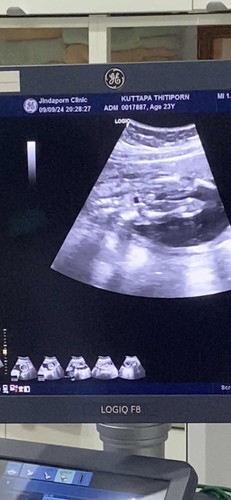

เพศหญิงหรือเพศชายช่วยดูให้หน่อยคะ

เเม่ๆคนไหนดูออกบ้างว่า ผญ หรือ ผช คะ ทางนี้ดูไม่ออก🤣🥰 ช่วยคอมเมตต่อยนะคะ

มีกลมๆเหมือนจะเป็นผู้ชายเลยค่ะ

เหมือนชายเลยค่ะแม่🥰

น่าจะผู้ชาย น่ะค่ะแม่

น่าจะชายนะค่ะแม่

น่าจะผู้ชายนะคะ

เป็นเด็กผู้ชาย

ผู้ชายค่ะแม่

ผช.ค่ะ

ผู้ชายค่ะ